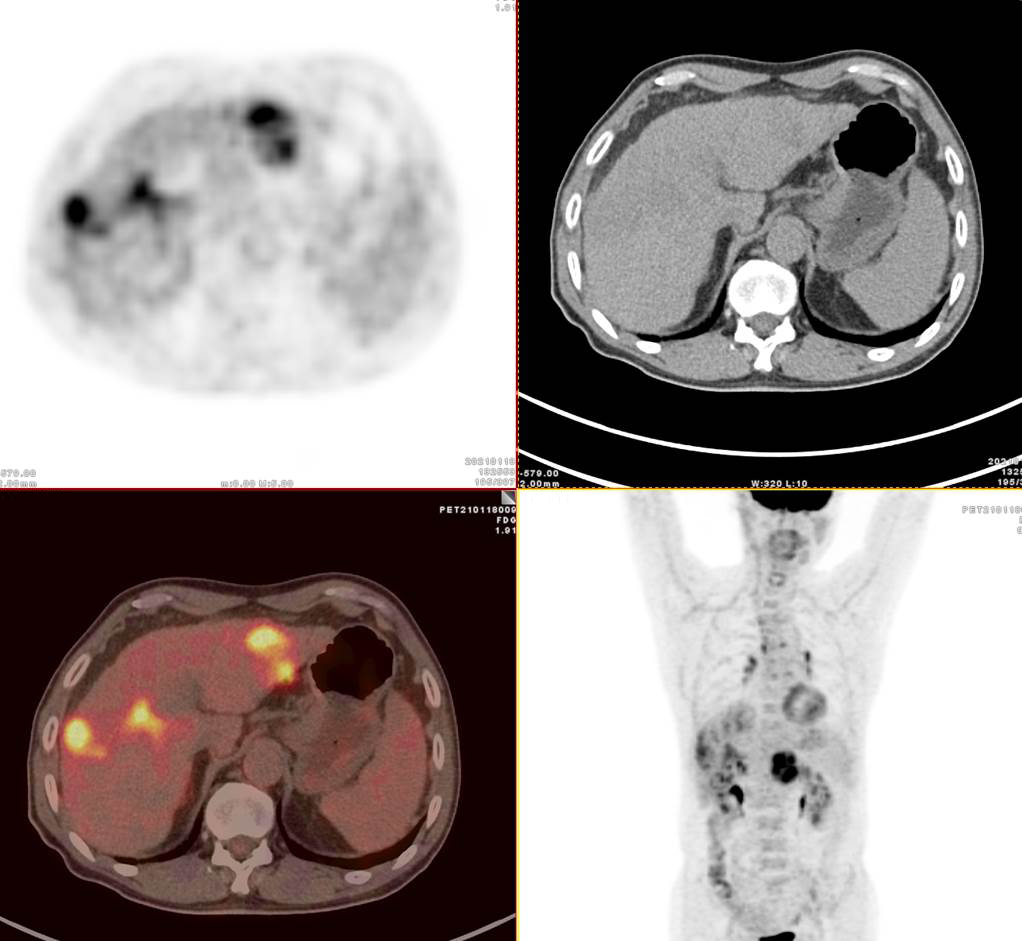

13歲男孩小新,因腹瀉就診,外院CT發(fā)現(xiàn)肝臟多發(fā)占位,考慮肝癌并肝內(nèi)轉(zhuǎn)移,肝硬化、門靜脈癌栓形成。為了查找病因及進行更深入的檢查,小新一家選擇進行全身的PET/CT檢查。據(jù)悉小新有乙肝病史10年。

PET/CT顯示肝臟明顯增大,肝內(nèi)見10.6x8.1cm稍低密度腫塊,F(xiàn)DG攝取不同程度最高,SUVmax 2.5-5.5。門靜脈增寬,F(xiàn)DG攝取不高,脾臟增大。

PET/CT診斷 :原發(fā)性肝細胞肝癌;門靜脈高壓